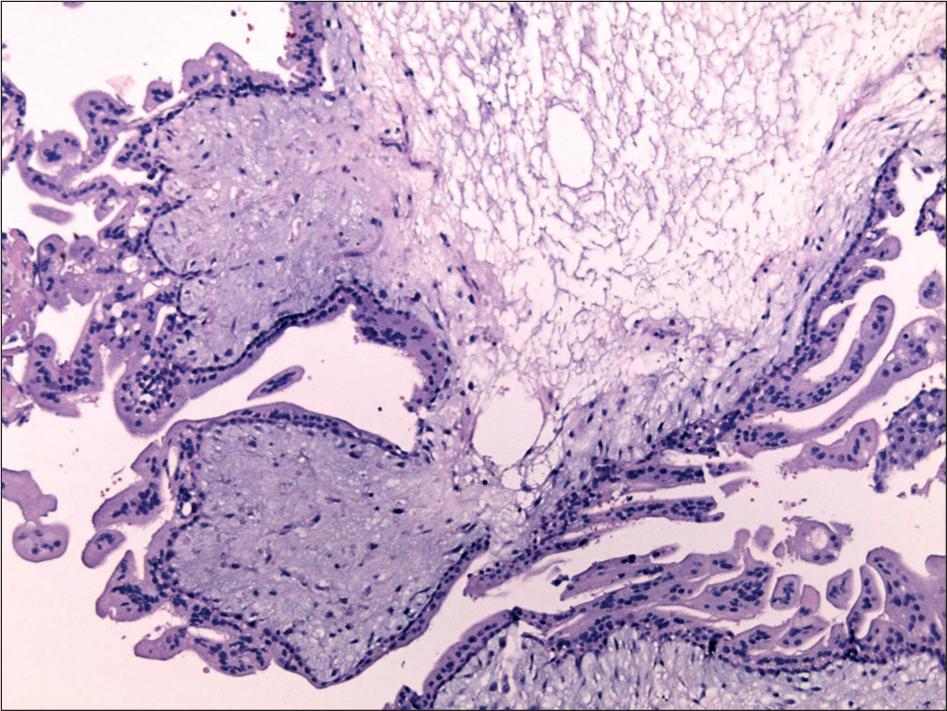

Histopathological characteristics of complete mole_

| Complete Mole | Absent or | Complete |

|---|---|---|

| Heterogenous population of villi | absent | 0 (0.0) |

| Circumferential trophoblastic proliferation | absent | 1 (12.5) |

| Cytotrophoblastic proliferation | absent | 3 (37.5) |

| Nuclear atypia | absent | 0 (0.0) |

| Karyorrhectic stromal debris | absent | 6 (75 0) |